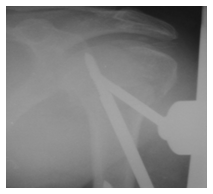

With patient under general anesthesia on a standard operating table with fluoroscopy control, Using fluoroscopy control, trial of humeral head reduction was performed and followed by reduction of the three or four-part fracture with intra operative manipulation using Kirschner wires. A Steinman pin in distal fragment was used as a joystick for traction as well as reduction. The reduction was accepted following Neer’s criteria for reduction.24 All the patients achieved acceptable closed reduction of their fracture. Two or three pins were inserted in proximal fragment and two pins were inserted in the humeral shaft and the fixator was applied (Figure 9).

Figure 9 Clinical picture of application of fixator – Note the severity of injury- with swelling and ecchymosis along with considerable soft tissue injury